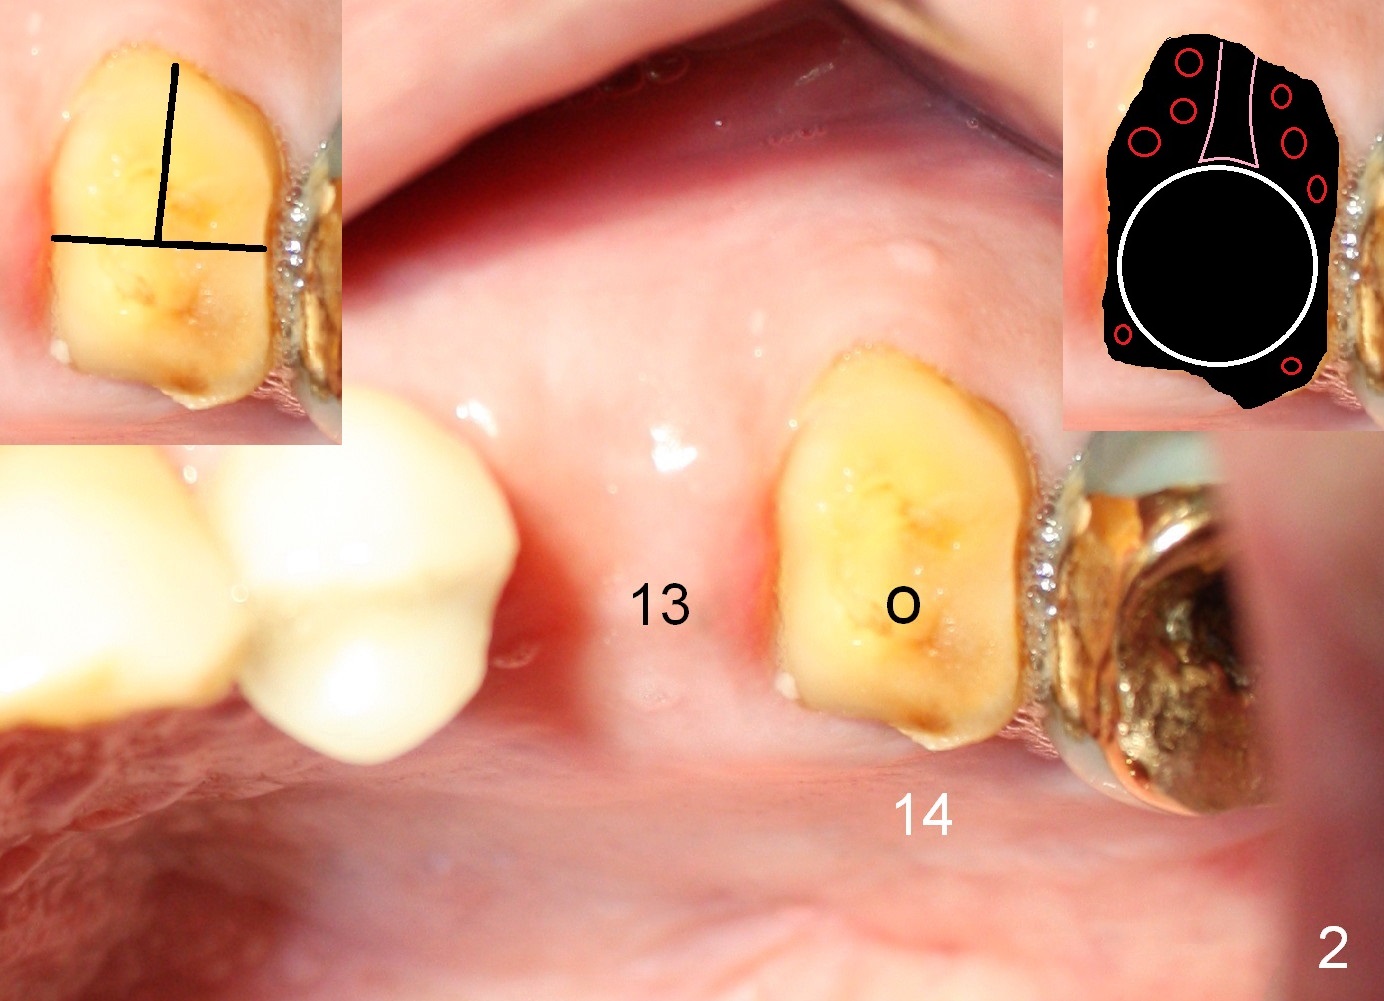

A 71-year-old man has multiple restorations, most of which are high noble crowns (Fig.0). He used to have a cantilever bridge involving the teeth #13 and 14 (Fig.1). It fractures (Fig.2,3). Considering the obliterated canals (Fig.1) and history of "bristle teeth", implants will be the best treatment option. The tooth #14 will be sectioned (Fig.3 upper left inset) for extraction. The osteotomy will be initiated in the septum slightly palatal, as shown by O in Fig.3 so that the immediate implant will be almost obliterating the socket mesiodistally (Fig.2 upper right inset white circle). The implant is also contacting the palatal wall of the socket and the buccal septal strut (pink outline) for primary stability. It appears that a 6x17 mm tissue-level implant is able to occupy the mesiodistal space (Fig.4) and that a 7 mm may be a better option. There is enough bone height for a 20 mm long implant.

An implant will be placed at the site of #13 at the same appointment. Bone will be harvested from the site of #13 while making osteotomy and transplanted into remaining sockets of #14 after implant placement (Fig.2 upper right inset red circles). If insertion torque is reasonably high for these 2 implants, an immediate provisional FPD (non-cantilever) will be fabricated to keep the papilla between the sites of #13 and 14 (Fig.3 *).